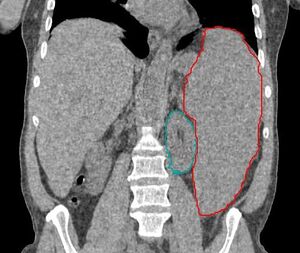

![]() | |

Blood smear from a person with myelodysplastic syndrome. A hypogranular neutrophil with a pseudo-Pelger-Huet nucleus is shown. There are also abnormally shaped red blood cells, in part related to removal of the spleen. | |